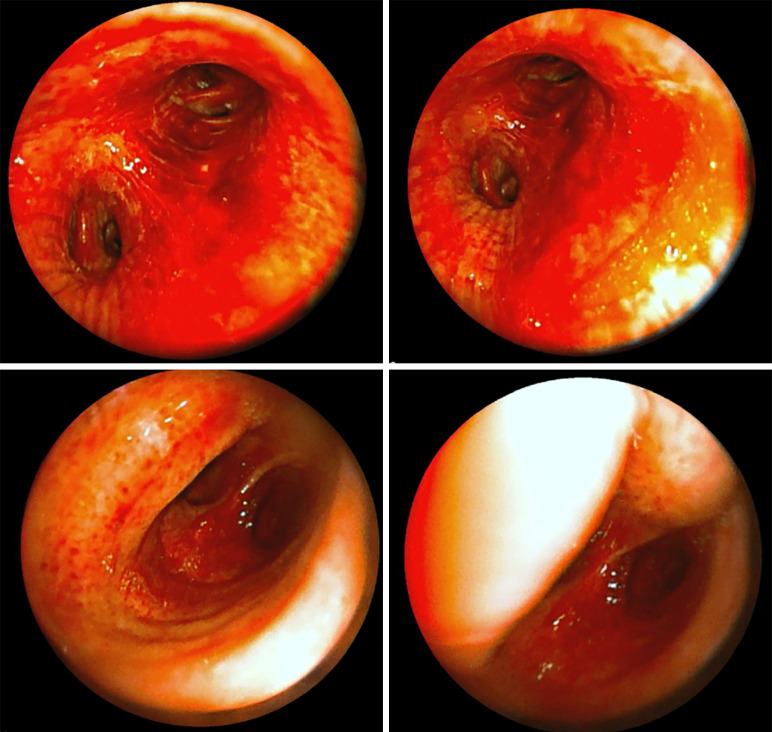

Case description: A 60-year-old obese male with no significant history of lung or cardiac disease presented to the emergency department with sudden-onset dyspnea, severe hemoptysis, palpitations, and tachycardia. Vital signs indicated hypertension (180/110 mmHg) and hypoxia [peripheral capillary oxygen saturation (SpO2) of 80% on room air]. The electrocardiogram (ECG) revealed sinus tachycardia but no right bundle branch block (RBBB). Laboratory tests were mostly unremarkable, and a computed tomography (CT) scan ruled out pulmonary embolism but showed diffuse bronchial wall thickening consistent with bronchitis or atypical pneumonia. During the clinical interview, the patient admitted to recent use of inhaled cocaine and amphetamines, leading to the diagnosis of early-stage "crack lung". After stabilization by administration of oxygen, bronchodilatators and prednisolone, the patient was discharged with follow-up care focusing on cessation of drug use and monitoring for potential lung damage. Bronchoscopically, there was no evidence of another cause of hemorrhage such as tumor growth.